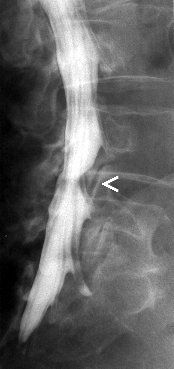

Myelografie

Myelografie is het in beeld brengen van het ruggenmergkanaal door middel van een contrasmiddel. Deze wordt door middel van een punctie ingespoten in de duraal zak in de lage rug. Er wordt dus in de rug geprikt zodat een naald door kan schuiven tussen de wervels tot in het ruggenmergkanaal. Dit kan gebeuren onder plaatselijke verdoving, maar dit is geen regel. Gesteld wordt dat er in elk geval moet geprikt worden. Er kunnen opnames genomen worden ter hoogte van de hals, borst of lage rug. Na de punctie worden er conventionele opnames gemaakt waarna de patiënt naar de CT-scan wordt gebracht om axiale beelden te maken in de regio waar zich mogelijk problemen voordoen.

Het is echter zo dat deze onderzoek steeds vaker vervangen wordt door een MRI vande rug, daar dit minder invasief is, minder risicos inhoudt en beter verdragen wordt door de patiënten.

Indicaties:

![]() | Het opsporen van een degeneratieve tussenwervelschijf |

![]() | Tumoraal proces tussen de wervels |

![]() | Trauma met fractuur of verplaatsing van een wervel |

![]() | Post operatieve problemen |